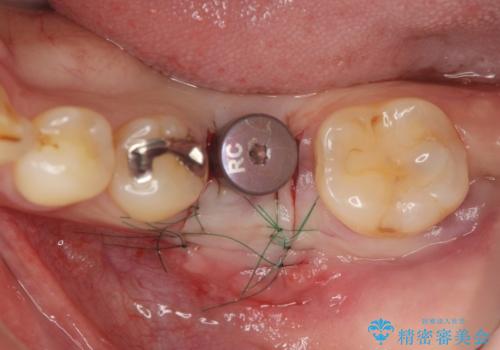

抜歯後ブリッジとインプラント治療を検討・相談し、より周囲の歯を削らずに済むインプラント治療を希望されたのでインプラントによる機能回復を計画します。

- 46.2万円(インプラント・チタンカスタムアバットメント・仮歯・ジルコニアクラウン)費用は治療当時の料金となります

- 外科手術のため、術後に痛みや腫れ、違和感を伴います